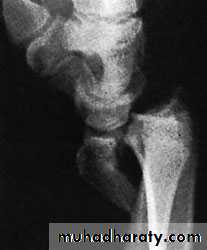

FRACTURED RADIAL STYLOID

This injury is caused by forced radial deviation of the wrist and may occur after a fall, or when a starting handle ‘kicks back’ – the so-called ‘chauffeur’s fracture‘The fracture line is transverse, extending laterally from the articular surface of the radius; the fragment, much more than the radial styloid, is oftenundisplaced.